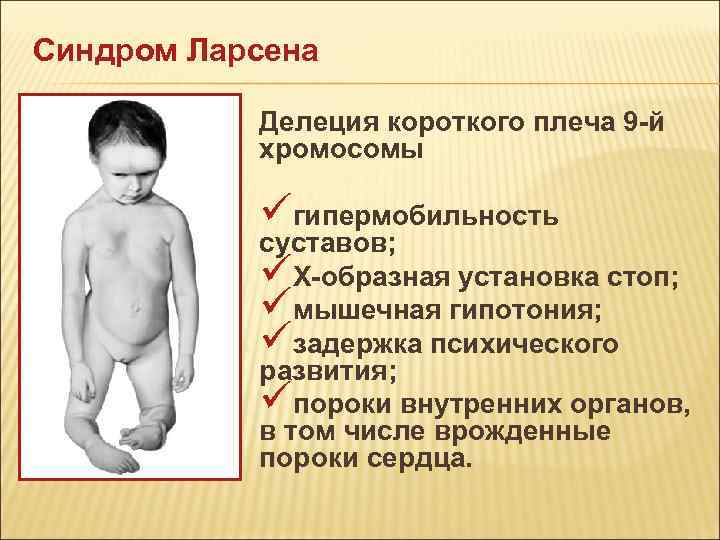

Ларсена йохансона

Ларсена йохансона 146 фото